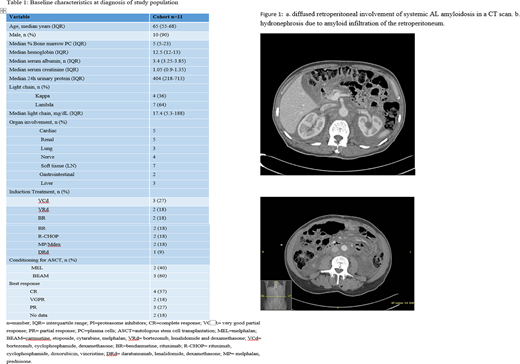

Figure 1 shows typical diffuse retroperitoneal involvement of AL amyloidosis on a CT scan.

We identified 11 patients with systemic AL amyloidosis and retroperitoneal involvement between January 2001 and December 2018. Median age at diagnosis was 65 years (range 50-72). Ten were male (91%) and one was female. Five patients had amyloid secondary to B cell lymphoma (4 Waldenstrom macroglobulinemia and 1 had follicular lymphoma). The involved light chain was lambda in 7 patients and kappa in 4 patients. All patients were diagnosed with retroperitoneal involvement of amyloidosis at presentation (not at progression). In 10 out of the 11 patients, amyloidosis in the retroperitoneum was confirmed by a core biopsy of the retroperitoneal tissue. Significant unintentional weight loss (more than 5 kg) at presentation was documented in six patients (55%). Seven patients (64%) had enlarged lymph nodes on the CT scan. Three patients had CT finding of calcifications, and the distribution pattern was diffuse in 7 patients (64%), while 4 patients presented with a mesenteric mass. Six patients (55%) had evidence of amyloid deposits in the bone marrow and 3 patients (27%) had a positive fat pad. Periorbital purpura was observed in one patient and none had macroglossia. Therapy regimens used are described in table 1. Five patients underwent an autologous stem cell transplantation (ASCT).

Eight patients (72%) presented with unilateral (N=2) or bilateral (N=6) hydronephrosis and 7 had nephrostomy tubes or stents inserted. The median follow-up from stent/nephrostomy tube insertion was 33 months (IQR 8-91). Regression of the deposition was documented in one patient and one patient was able to have his nephrostomy tube removed. One patient (9%) developed end stage renal disease requiring dialysis.